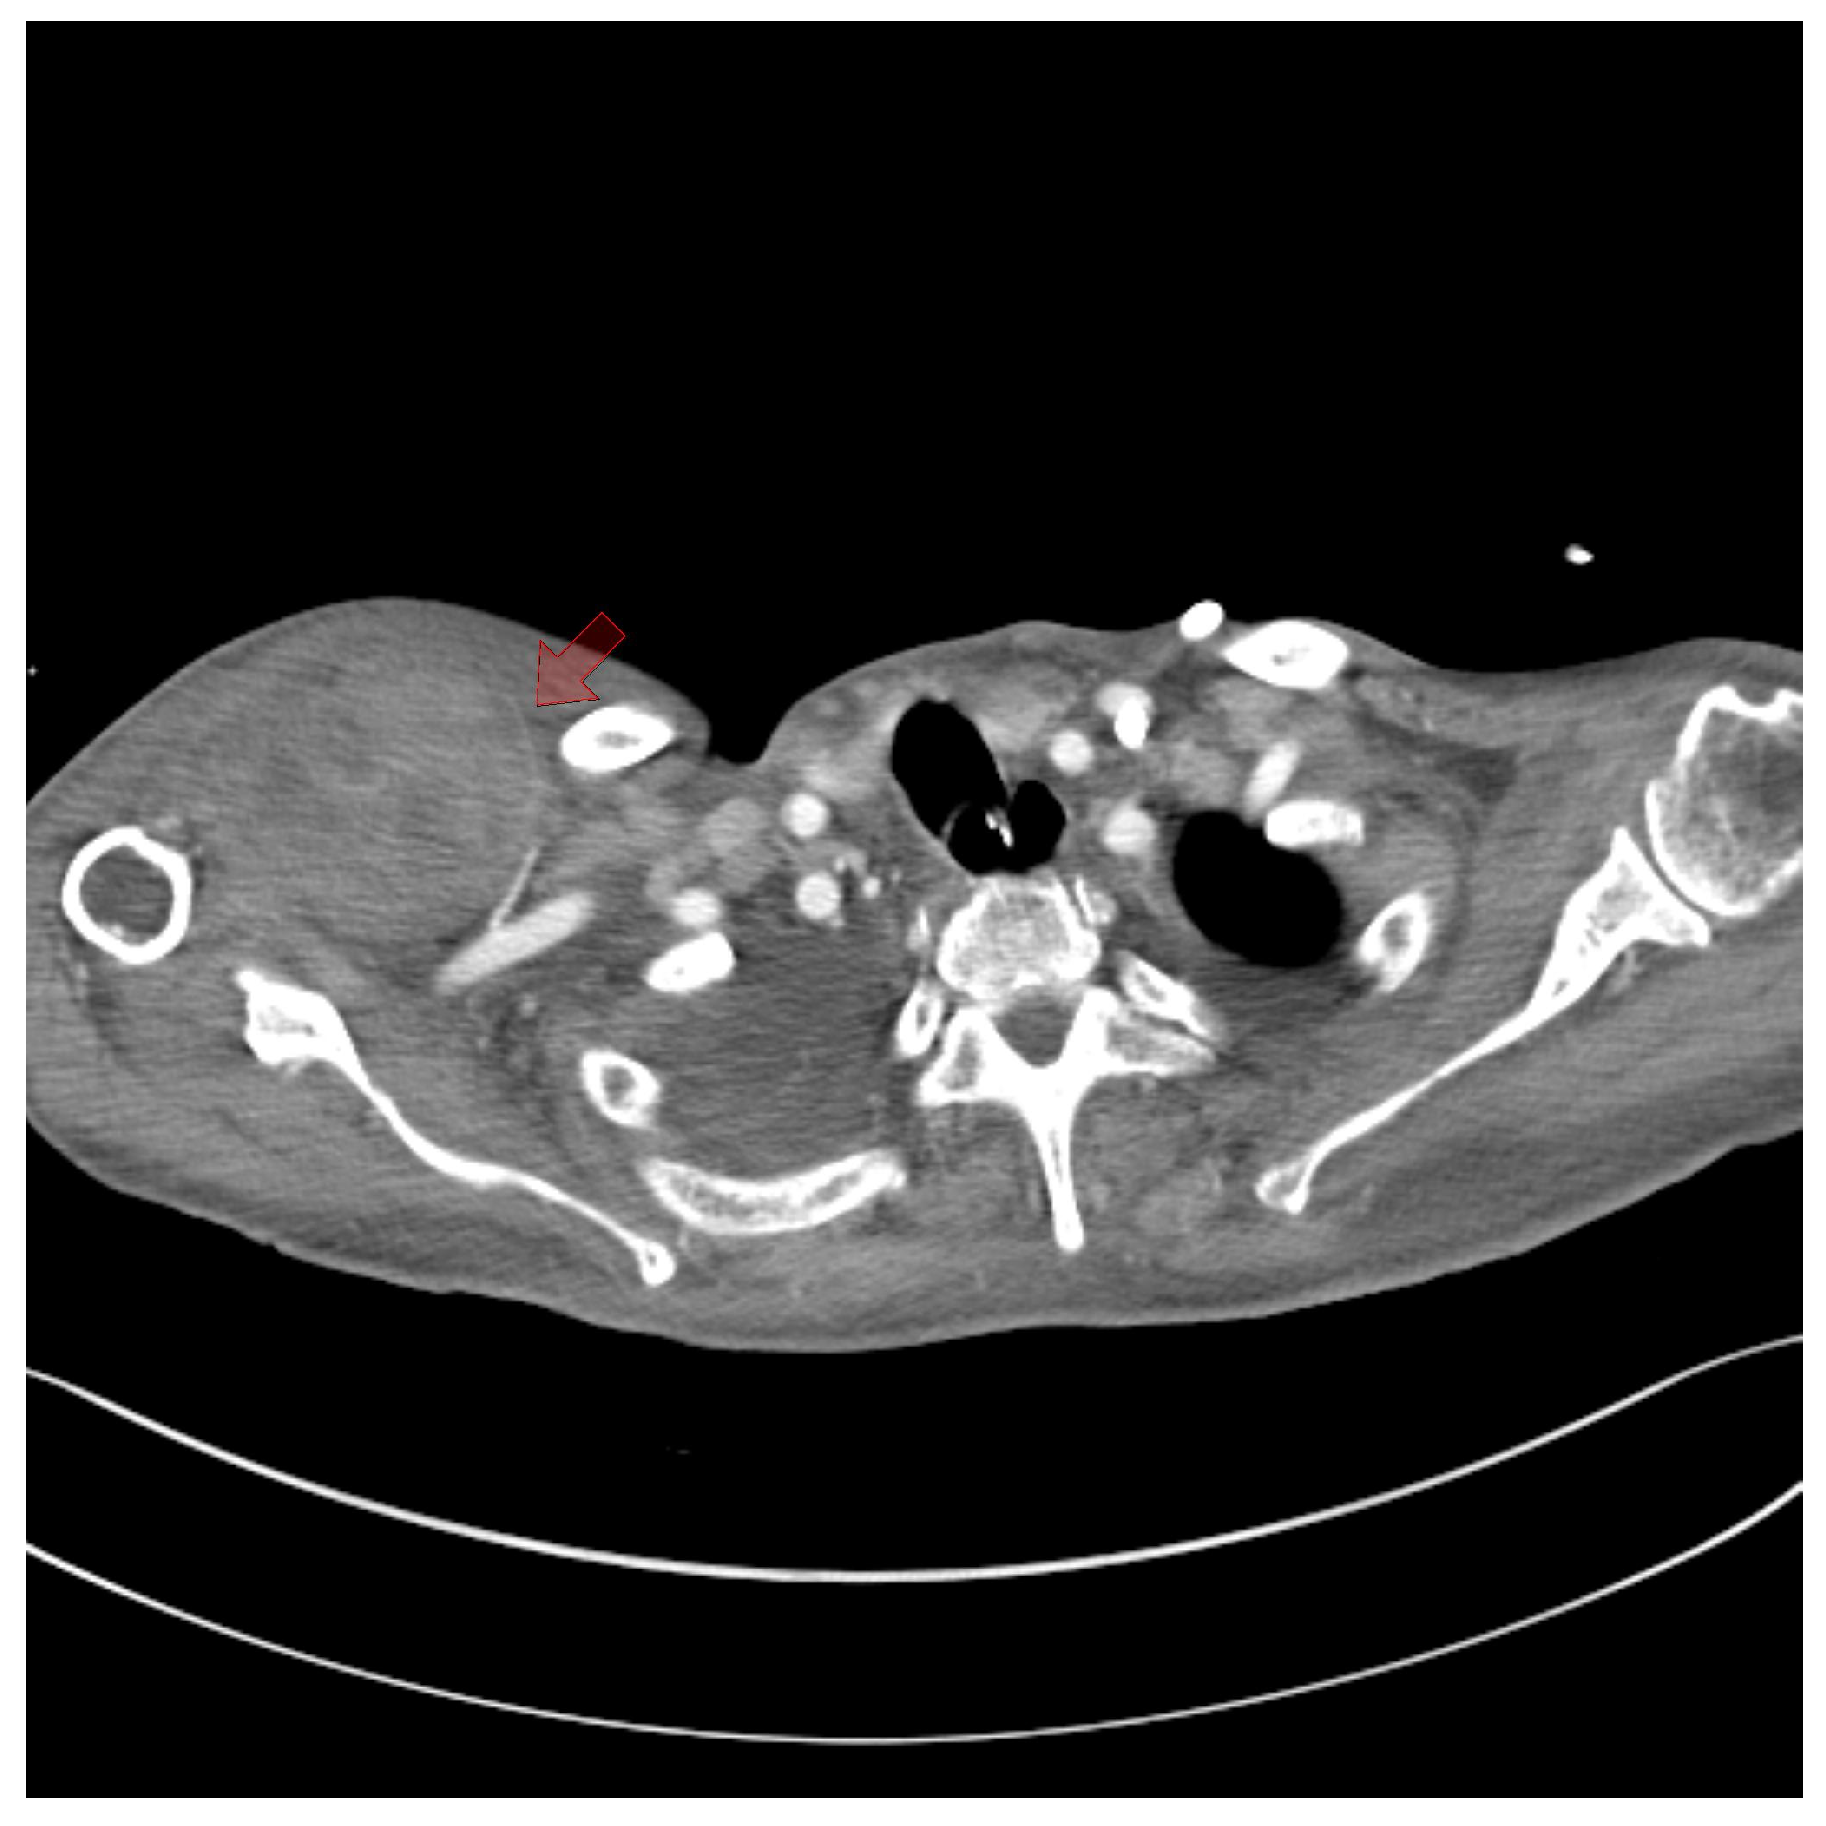

Figure 2. Chest computed tomography angiography. (A) A coronal view shows intact vessel patency in the subclavian artery and axillary artery (red arrow), which could have contributed to the hematoma in the chest wall. (B) No extravasation or abnormalities were observed in the thoracoacromial artery (red arrow). (C) No abnormalities were observed in the main pedicle of the lateral thoracic artery (red arrow).

Chest computed tomography (CT) angiography revealed a newly formed 18.7 × 13.1 × 9.6 cm hematoma in the right upper anterior chest wall, with no signs of active bleeding or evidence of a pseudoaneurysm or malignant tumor (Figure 1 and Figure 2). On the fourth day post-onset, transarterial angiography was conducted via the right common femoral artery. Angiograms of the right subclavian artery, right internal mammary artery, and thoracic aorta showed no active bleeding, precluding the possibility of embolization. To manage the resulting anemia, 2 units of PRCs were transfused.

On the fifth day, surgical exploration revealed a large hematoma beneath the pectoralis major muscle. The hematoma had solidified and showed no signs of infection; culture results were negative. Bleeding was identified from a branch of the lateral thoracic artery within the deep portion of the pectoralis major muscle, as observed on CT angiography (Figure 3). The procedure involved removing the hematoma and ligating the vessel, followed by irrigation, placement of a closed suction drain, and primary closure. The surgery was completed with a mild compressive dressing (Figure 4).